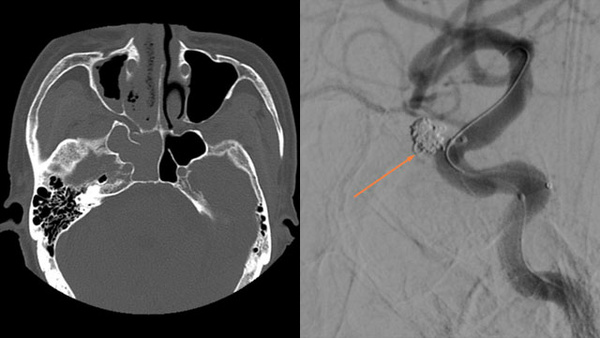

Pseudoaneurysm of the internal carotid artery due to sphenoid sinusitis

Aneurysms